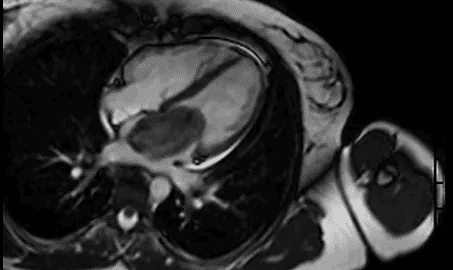

A Ressonância Magnética do Coração é uma metodologia extremamente útil na identificação de inúmeras doenças cardíacas podendo ser utilizada na investigação das doença arterial coronariana (isquemia e viabilidade miocárdicas), miocardiopatias, cardiopatias congênitas, doenças do pericárdio e massas cardíacas. É o método padrão ouro para avaliação dos volumes / função ventricular e caracterização tecidual in vivo.